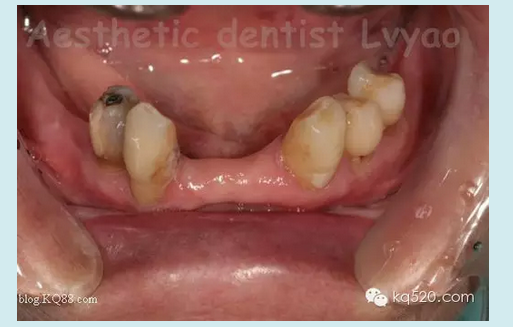

本病例在去年完成,患者是我的親人,現(xiàn)在修復(fù)體用的很好很舒適?;颊呱项M牙良好,下頜余留牙左下345良好,右下34有不同程度的牙槽骨吸收,右4松動(dòng)2度、右3松動(dòng)1度,臨床冠根比失調(diào)。原患者使用普通支架活動(dòng)義齒,現(xiàn)因基牙問(wèn)題等因素導(dǎo)致使用不佳,以保存基牙的原則等因素,本人設(shè)計(jì)了套筒冠與栓體栓道式附著體聯(lián)合應(yīng)用的修復(fù)技術(shù)。有關(guān)文獻(xiàn)報(bào)道,對(duì)于患者牙列缺損 少量基牙伴牙槽骨吸收或牙周病,不宜固定修復(fù)又對(duì)美觀(guān)、功能、舒適要求高??刹捎锰淄补谂c栓體栓道式附著體修復(fù)技術(shù)聯(lián)合的方法,此方法充分利用了栓體栓道式附著體固位力強(qiáng),義齒清洗時(shí)仍可維持垂直距離以及其固位體隱蔽和套筒冠技術(shù)的良好的基牙保護(hù)性能及可以在垂直及水平方向都能提高義齒的固位和穩(wěn)定性等優(yōu)點(diǎn)。有學(xué)者研究調(diào)查,發(fā)現(xiàn)套筒冠與栓體栓道式附著體聯(lián)合應(yīng)用的修復(fù)技術(shù)具有美觀(guān)、舒適、固位穩(wěn)定性良好、咀嚼效率高、保存保護(hù)基牙等優(yōu)點(diǎn)。實(shí)驗(yàn)表明牙周病患者能較快地適應(yīng)套筒冠義齒,咀嚼功能有所提高;套筒冠義齒具有良好的夾板固定效果,顯著降低牙周病患牙的松動(dòng)度,顯著減小牙周病患牙的牙周袋深度。

此病例正是如此,套筒冠主要的作用是保存維持了嚴(yán)重牙槽骨吸收的右下34基牙,改善了原基牙的臨床冠根比,縮短臨床冠高度大大減輕了對(duì)基牙承受的牙合力等其他應(yīng)力,減緩了牙槽骨的吸收,維持了基牙的使用壽命,再利用栓體栓道式附著體幫助,應(yīng)力分布更為均勻,從而修復(fù)后達(dá)到了非常好的效果。說(shuō)了那么多,還是看看病例照片吧:

修復(fù)前口內(nèi)影像